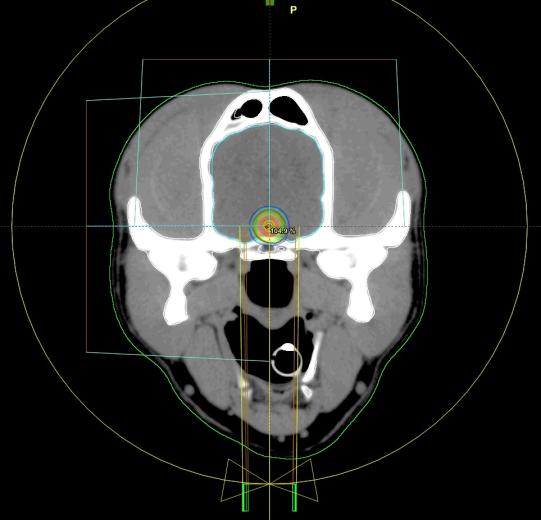

Die Besitzer entscheiden sich für die Bestrahlung, welche erfolgreich und ohne Nebenwirkungen verläuft: Der Geschwulst wird in Narkose mehrmals von mehreren Seiten bestrahlt - so erhält das Zielgebiet (rote Region, siehe unten) die maximale Strahlendosis, währenddem das umliegende Gewebe eher verschont bleibt.

Planungs-CT der Bestrahlung - der Tumor erhält die höchste Strahlendosis (roter Bereich) - Bildmaterial: Tierspital Zürich, Abteilung für Bildgebende Diagnostik und Abteilung Radio-Onkologie